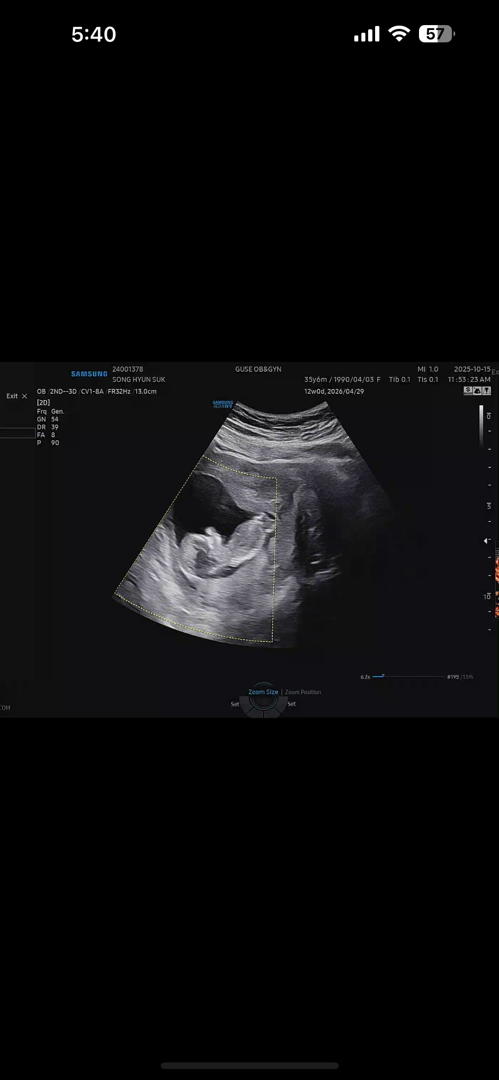

12주차 각도법 봐주세요

각도법 저는 잘 볼줄 모르겠어서 ㅜㅜ 투표ㅠ한번씩 부탁드립니당 ㅎㅎ